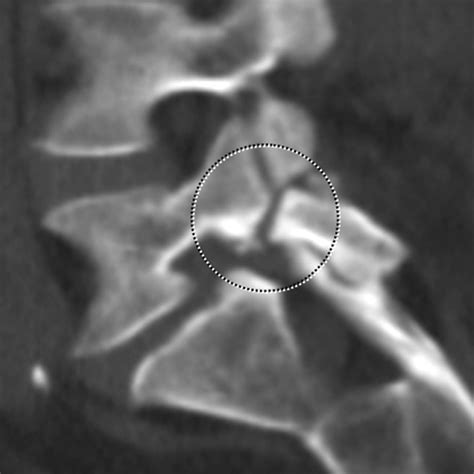

Patients Are Worried About 4mm Anterolisthesis After Recent Scans